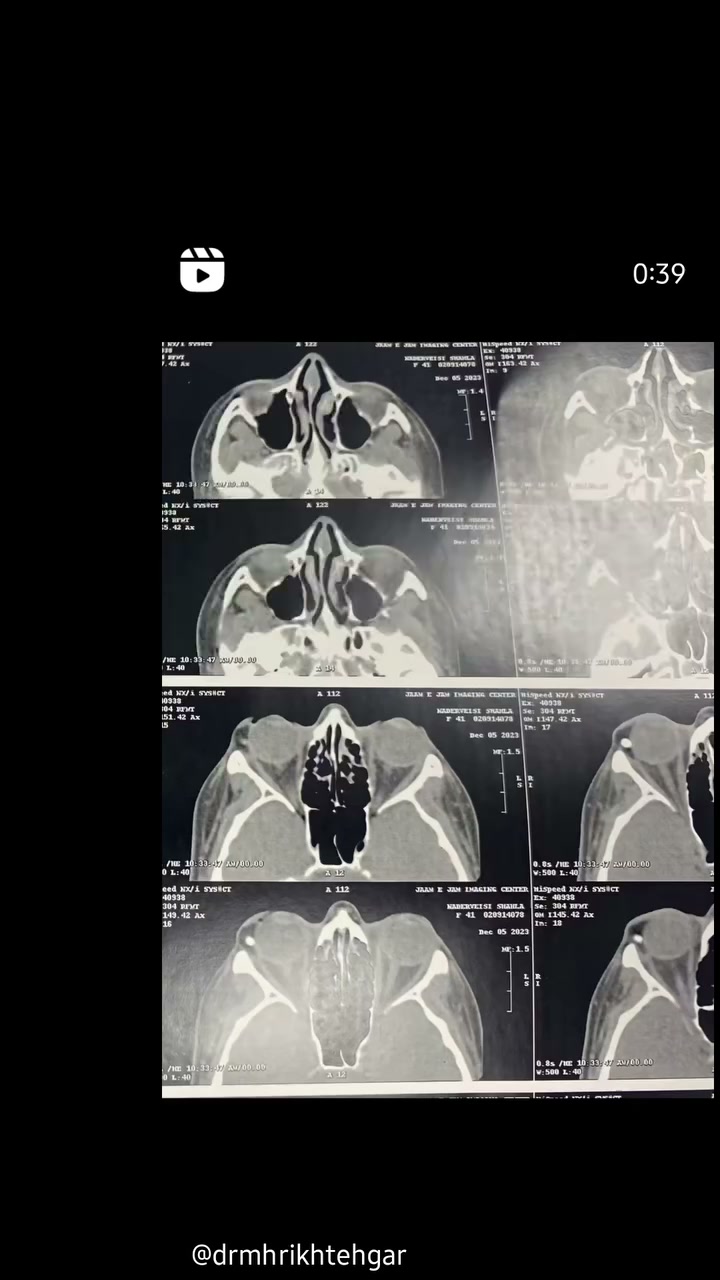

تومور